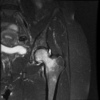

Diagnosis?

Transient osteoporosis of the hip

- Ddx for MRI - AVN (has serpigenous dark lines and involves more the subchondral femoral head)

- Bones is lucent on X-ray which looks very different than AVN (sclerotic)

- Regional migratory osteoporosis is similar however affects different joints